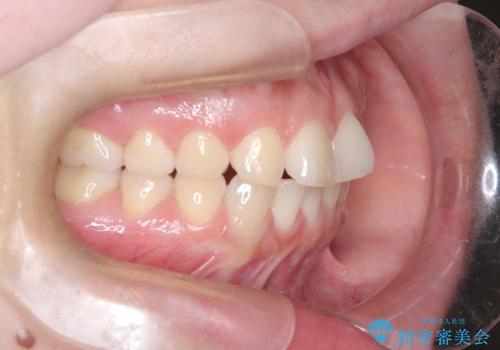

- 「歯の捻じれとがたつき」を主訴に来院された患者様です。

軽度な捻転と叢生だったため、インビザラインのモデレートで治療を行いわずか半年で治療を終える事が出来ました!

目立たないマウスピース矯正【インビザライン】を使用し、

わずか6ヵ月で歯並びがキレイに整いました!

矯正後は、リテーナー(保定装置)を使用し後戻りを防止中です。